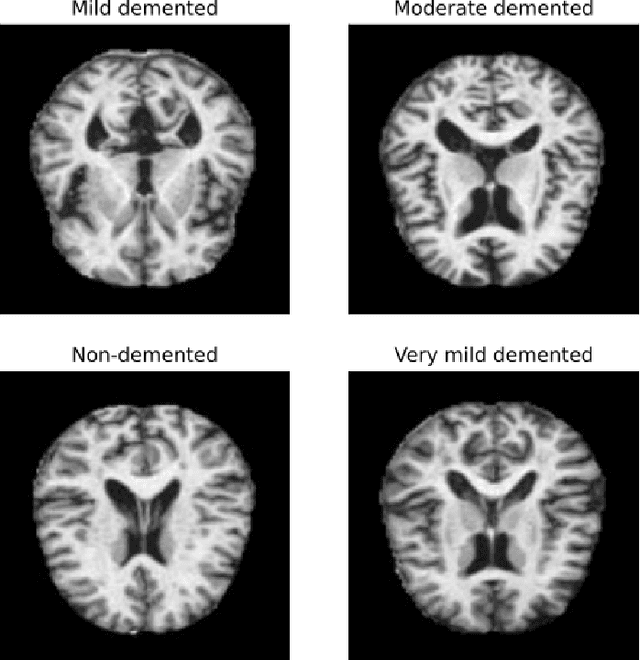

Abstract:Federated learning is a distributed learning technique that allows training a global model with the participation of different data owners without the need to share raw data. This architecture is orchestrated by a central server that aggregates the local models from the clients. This server may be trusted, but not all nodes in the network. Then, differential privacy (DP) can be used to privatize the global model by adding noise. However, this may affect convergence across the rounds of the federated architecture, depending also on the aggregation strategy employed. In this work, we aim to introduce the notion of metric-privacy to mitigate the impact of classical server side global-DP on the convergence of the aggregated model. Metric-privacy is a relaxation of DP, suitable for domains provided with a notion of distance. We apply it from the server side by computing a distance for the difference between the local models. We compare our approach with standard DP by analyzing the impact on six classical aggregation strategies. The proposed methodology is applied to an example of medical imaging and different scenarios are simulated across homogeneous and non-i.i.d clients. Finally, we introduce a novel client inference attack, where a semi-honest client tries to find whether another client participated in the training and study how it can be mitigated using DP and metric-privacy. Our evaluation shows that metric-privacy can increase the performance of the model compared to standard DP, while offering similar protection against client inference attacks.